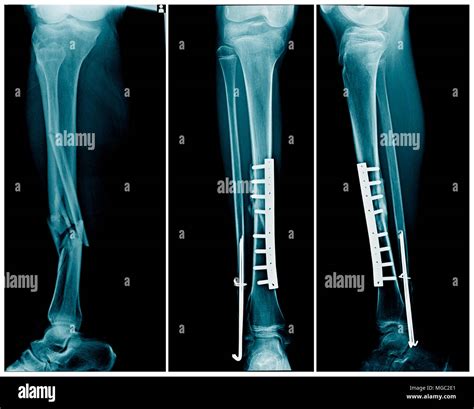

• X-rays: These are the primary imaging tool used to confirm the presence and type of fracture.

• Surgery: In severe cases, surgery may be required to realign the bones and stabilize them with plates, screws, or rods.